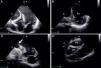

A recuperação inicial do doente foi lenta e arrastada, mas após a alta tem-se mantido clinicamente estável, em classe II NYHA. Repetiu ecocardiograma 3 meses após a intervenção cirúrgica que mostrou VE de dimensões normais, com compromisso ligeiro da função sistólica global e patch de ventriculoplastia normalmente inserido (fig. 7).

Ecocardiograma transesofágico bidimensional, eixo curto em sístole (painel A) e diástole (painel B) e 4 cavidades (em diástole, painel C) que mostra ventrículo esquerdo de dimensões normais, com função sistólica ligeiramente deprimida e patch de ventriculoplastia normalmente inserido e sem imagens de fluxo através do mesmo.